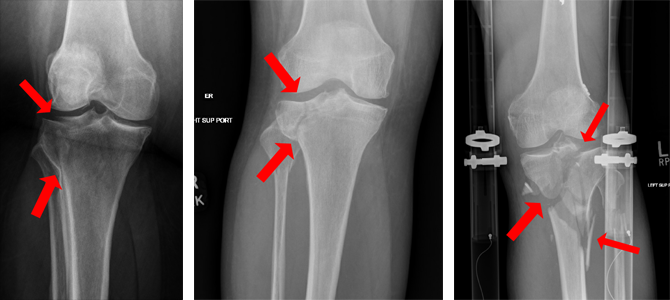

Figure 3: Intraoperative view showing a tibial plateau fracture before fixation.

Figure 4: Intraoperative image demonstrating reduction and provisional fixation with K-wires.

Figure 5: Post-fixation image illustrating plate and screw constructs used for stabilization.